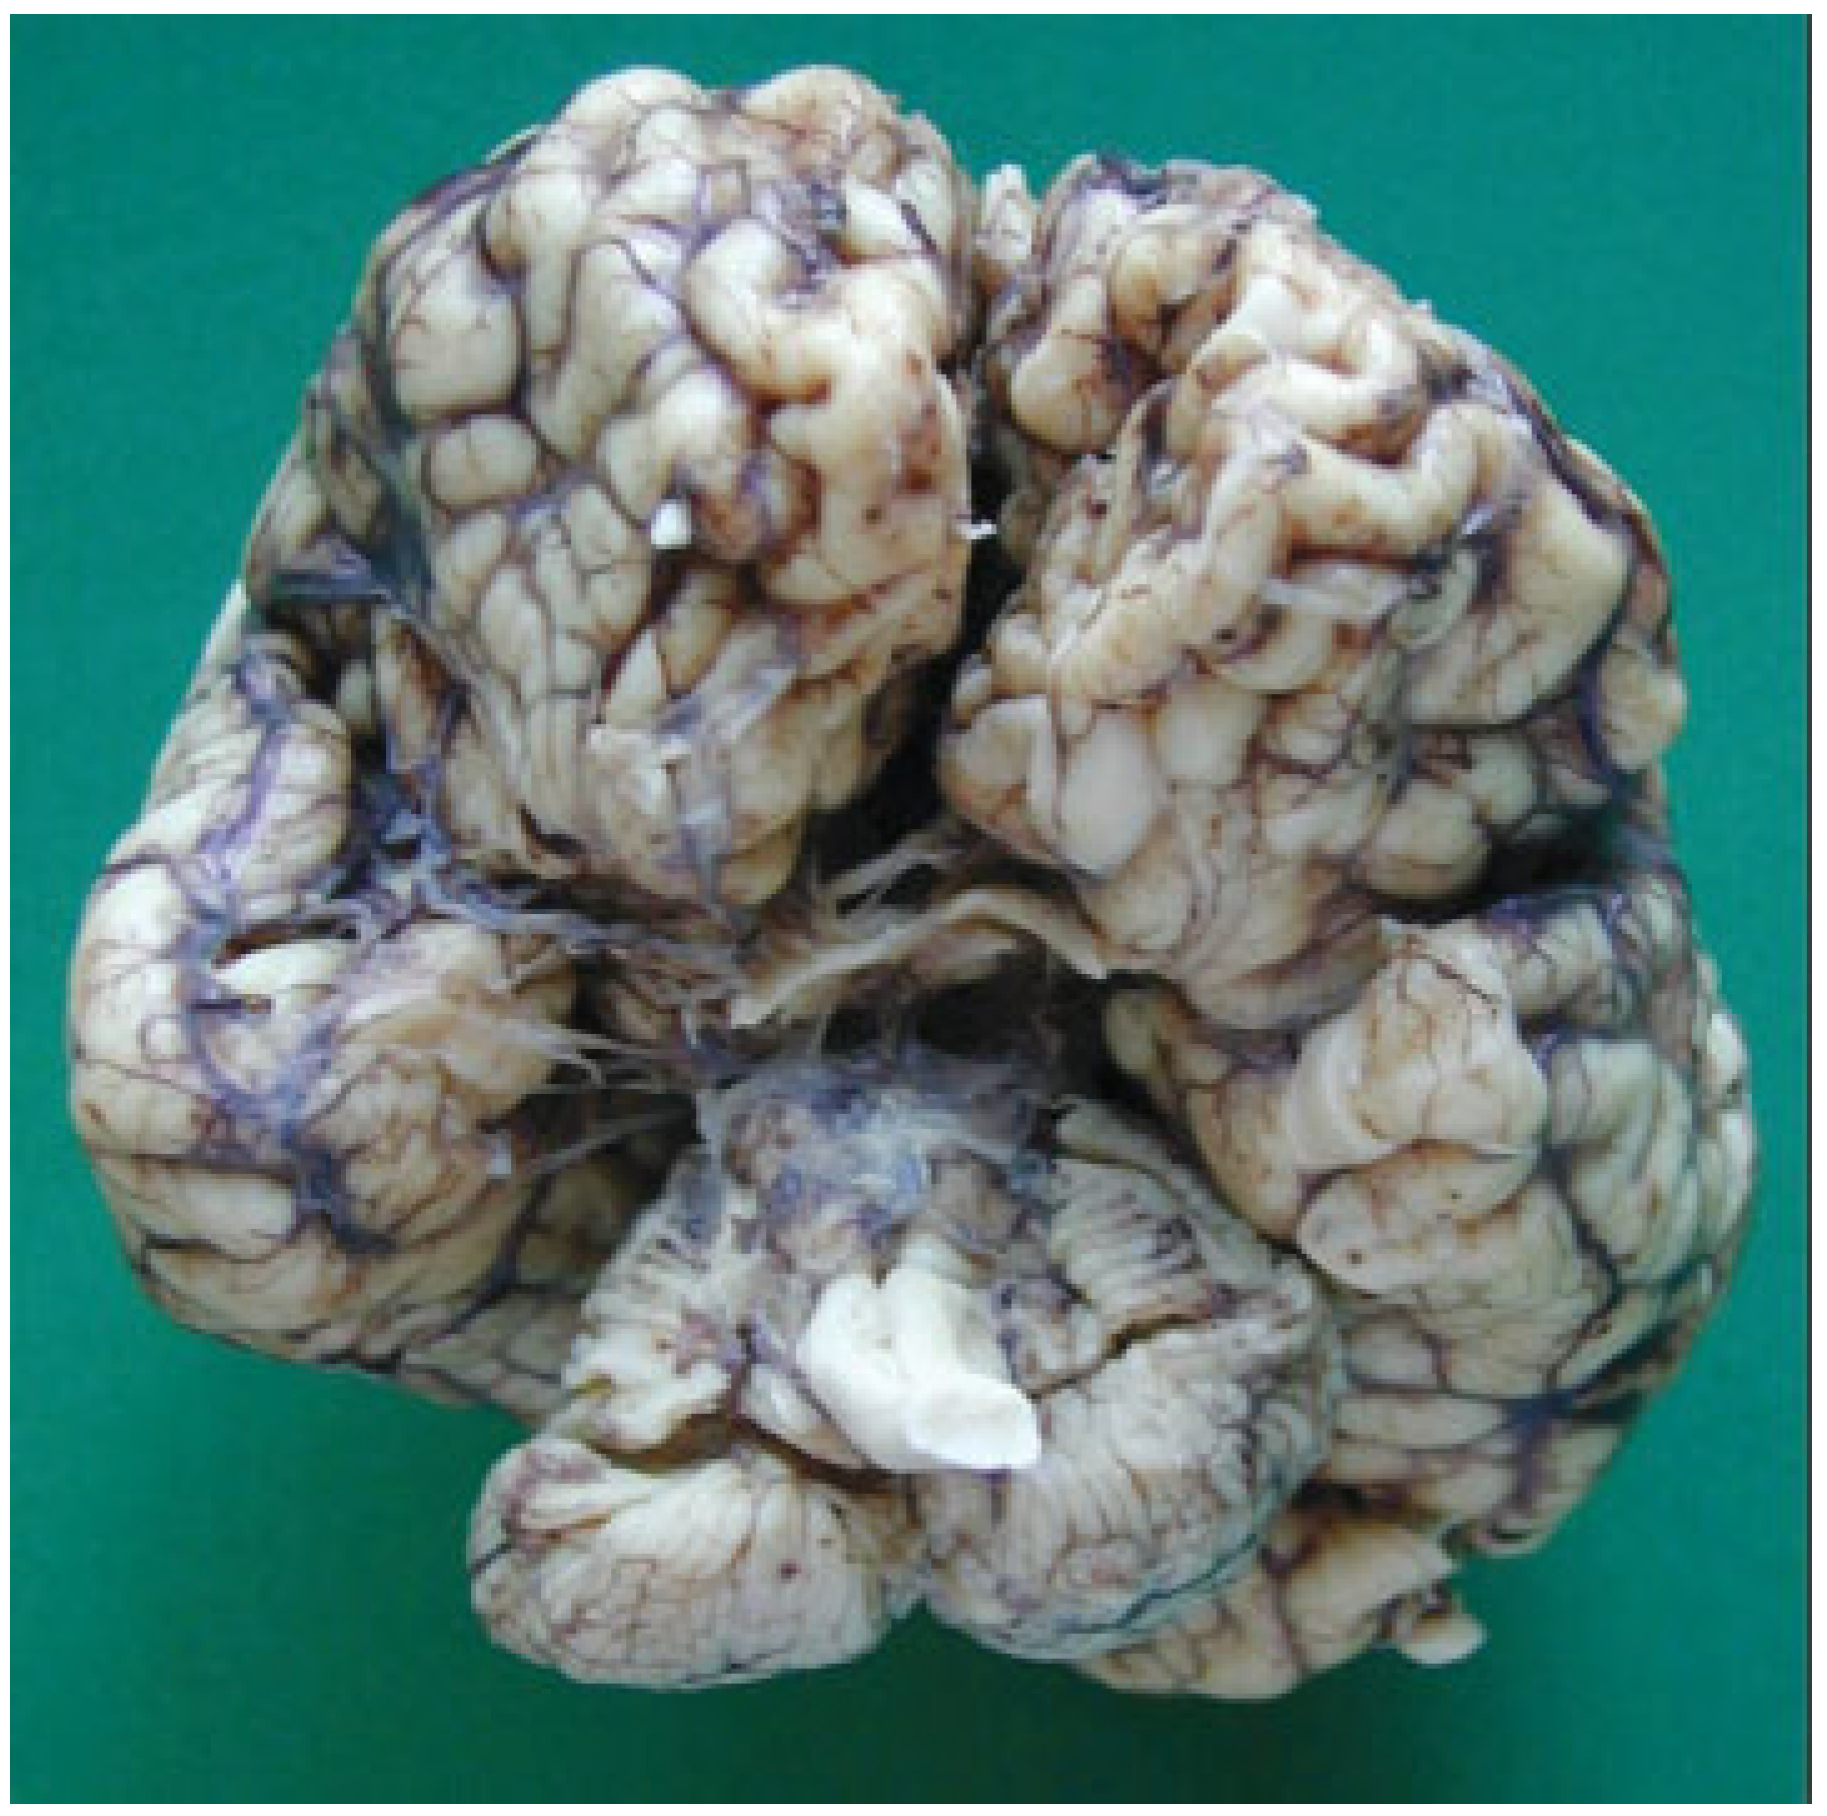

The autopsy study described a girl, 2 months and 20 days old, with karyotype (46,XX). She had frontonasal malformation (hypertelorism, broad nasal bridge, bifid nasal tip and anterior cranium), macrostomia, retrognathia, and bifid tongue. She also presented maxillomandibular bony fusion and fusion of the tongue to the palate and to the inferior lip by a hairy polyp (Figure 8), both corrected surgically. In the cranium, the sella turcica was broadened (Figure 9), with little prominence of the clinoid apophyses and with two cavities that contained two complete hypophyses with two infundibulums (Figure 10). The three cranial fossae were narrowed anteroposteriorly. The central nervous system (CNS) had both olfactory bulbs and corpus callosum agenesis (Figure 11 and Figure 12), anomalous morphology of the brain stem and spinal cord (Figure 13), and neuronal heterotopia in occipital white matter and leptomeningeal heterotopia.

Figure 11.

Olfactory bulbs agenesis.